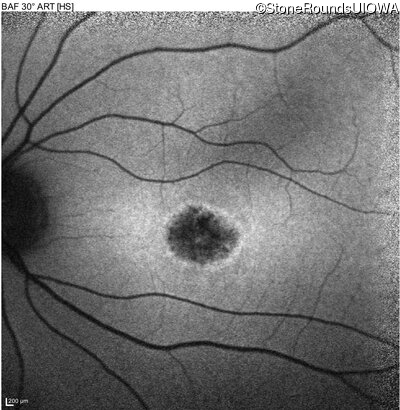

AR Stargardt Disease (IIA)

Age at visit:

14 years

OD

OS

20/125 -2

20/25 +2

AR Stargardt Disease

ABCA4

Gly1961Glu GGA>GAA

Asp1613 del1gA

AR